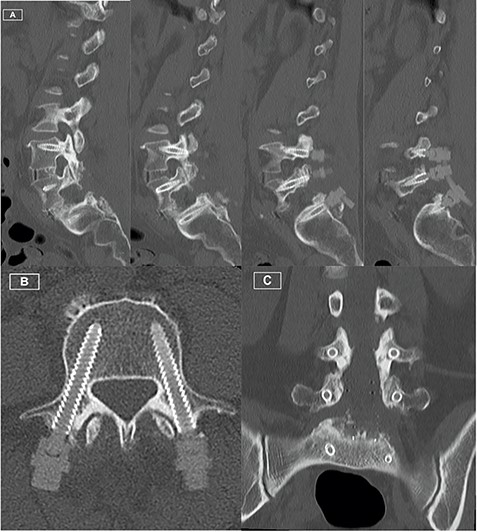

Postoperative CT Lumbar spine. (A) Sequence of sagittal slices demonstrating excellent definition of screw trajectory. (B) Axial slice through L4 pedicles demonstrating definition of screws and distinction from bony cortex. (C) Coronal slice demonstrating screws at all levels with no peri-structural artifact.